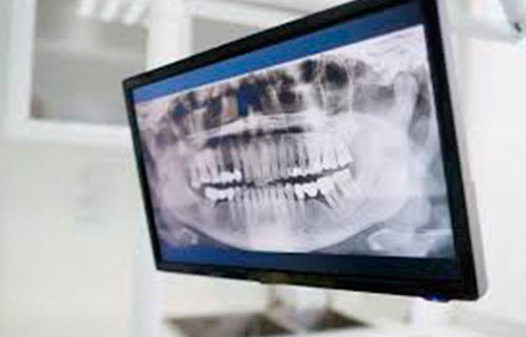

Se trata de una radiografía panorámica dental que brinda una imágen completa y única a la vez de dientes, maxilares y mandíbula.

Y ofrece una visión general, aporta información vital para determinar las dolencias que afectan y los tratamientos odontológicos que habrá que llevar a cabo.

● Ortopantomografía